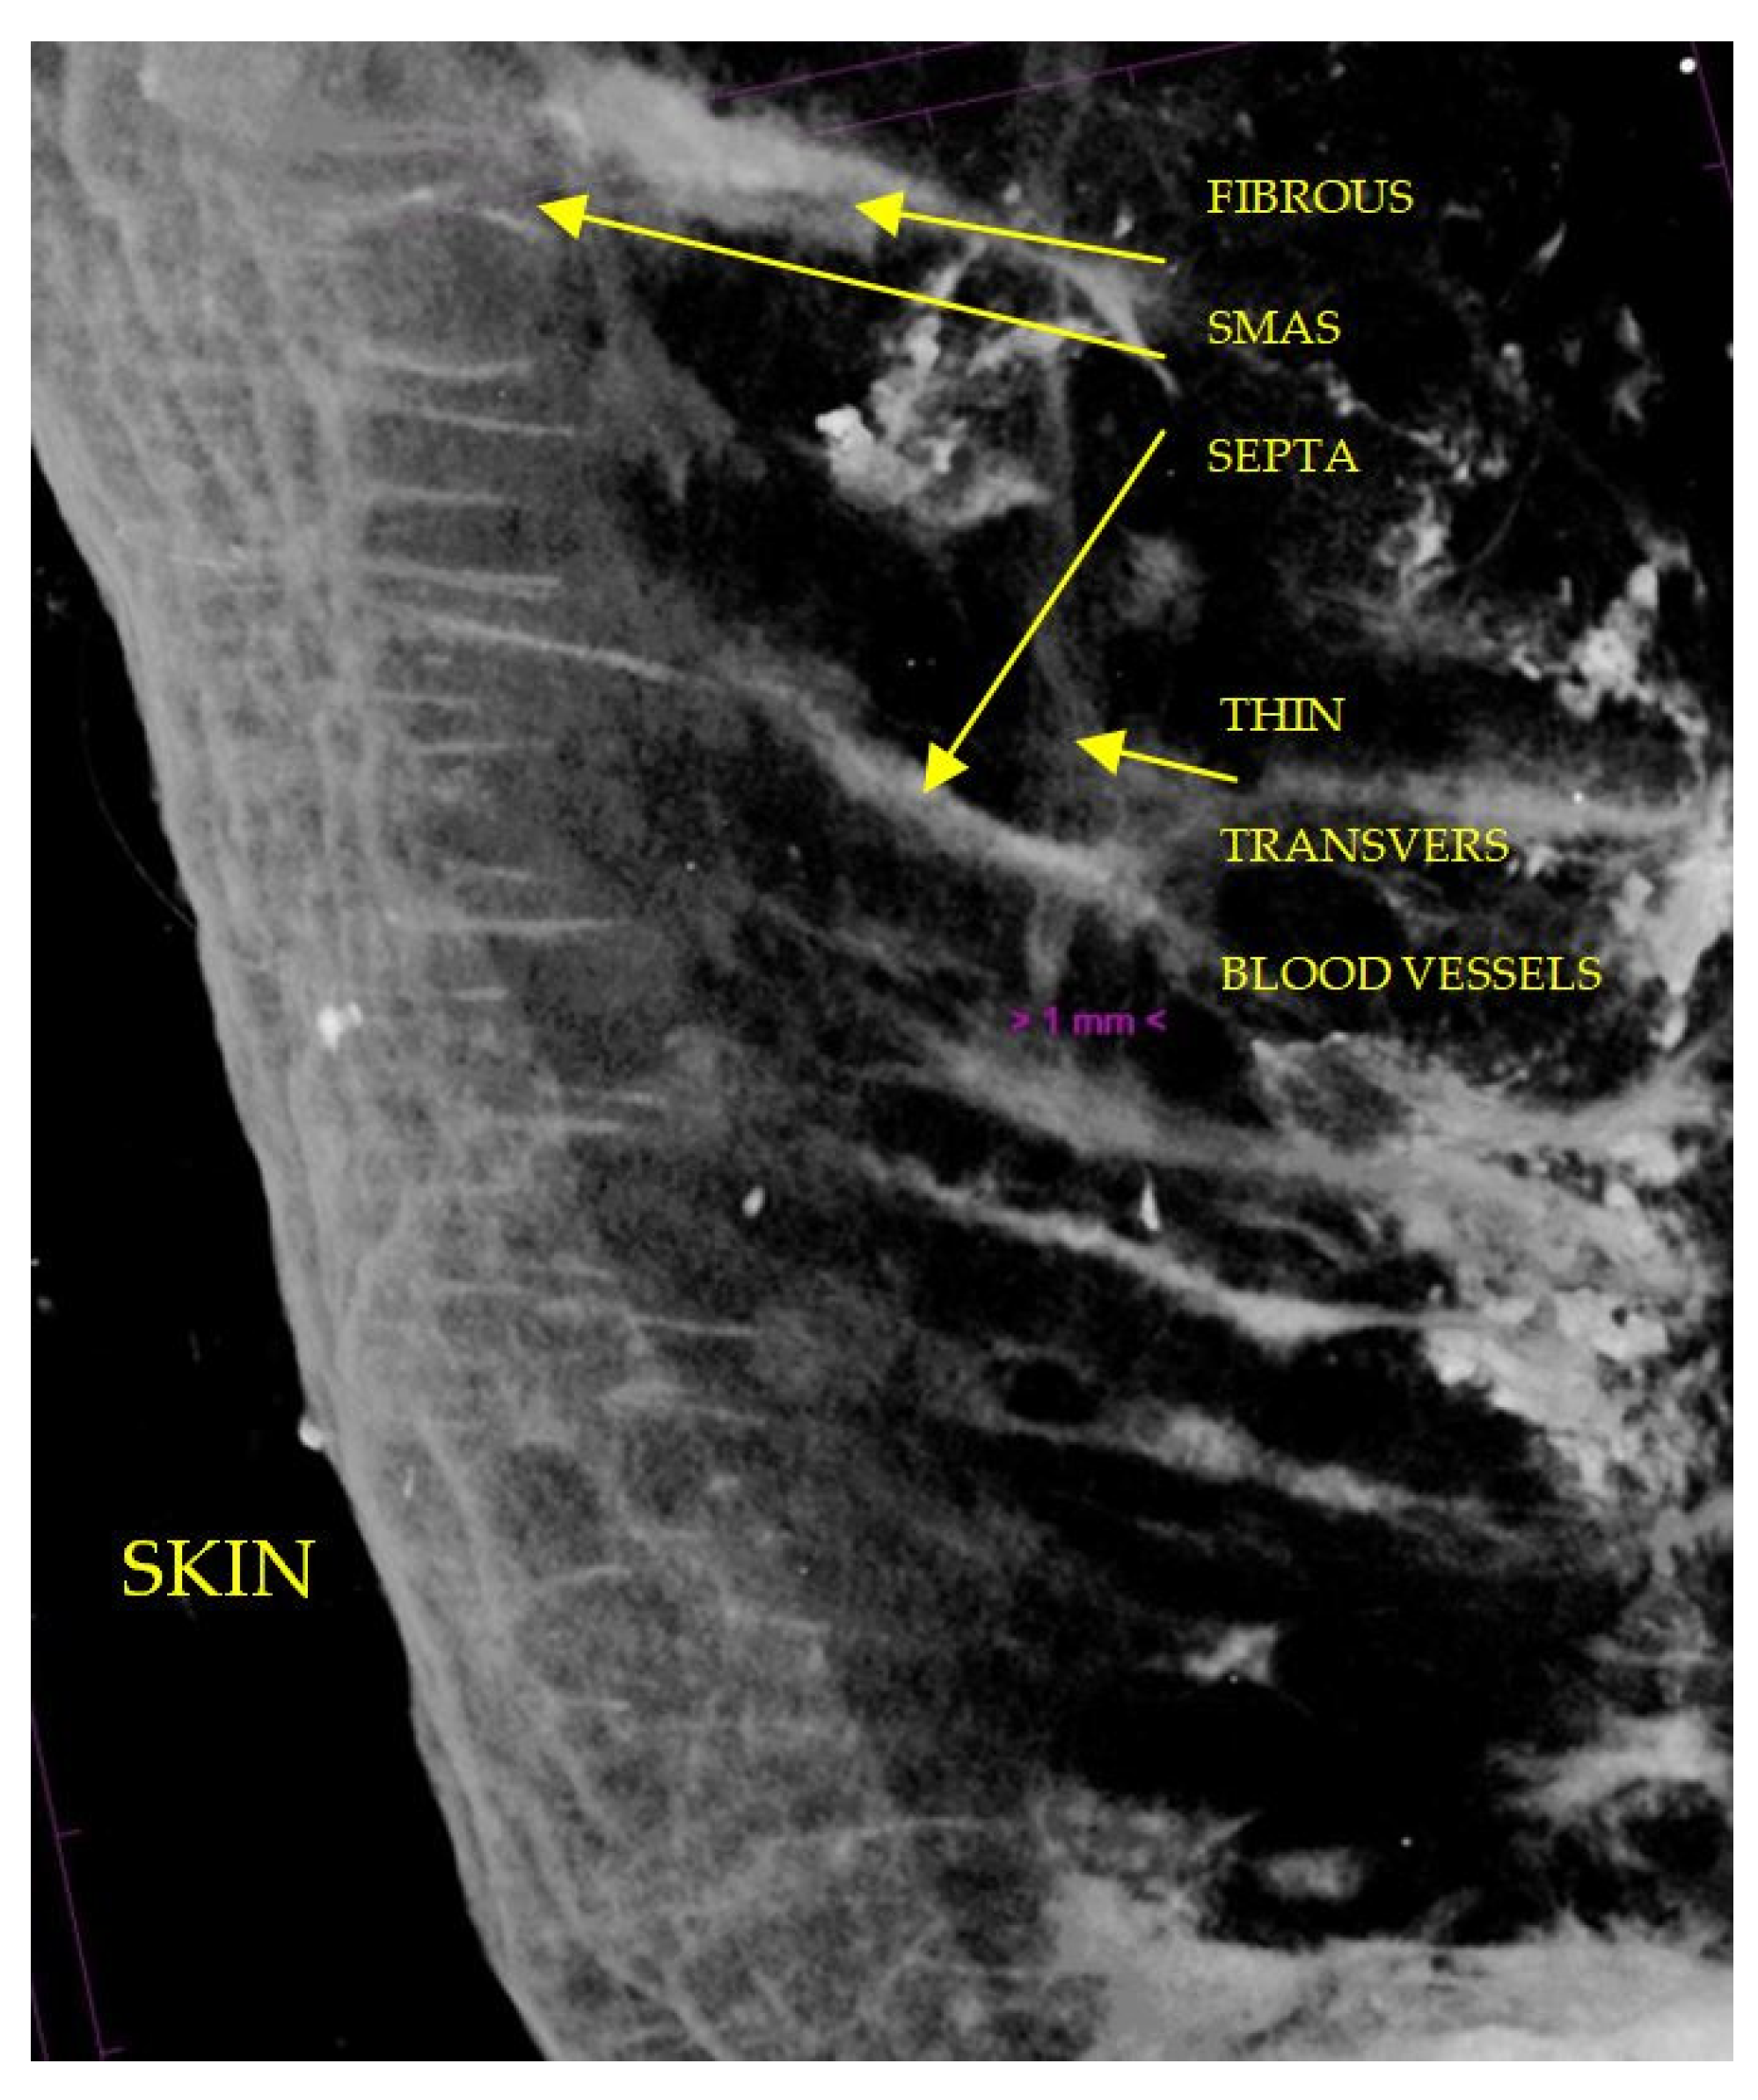

3.2. Micro-CT Study